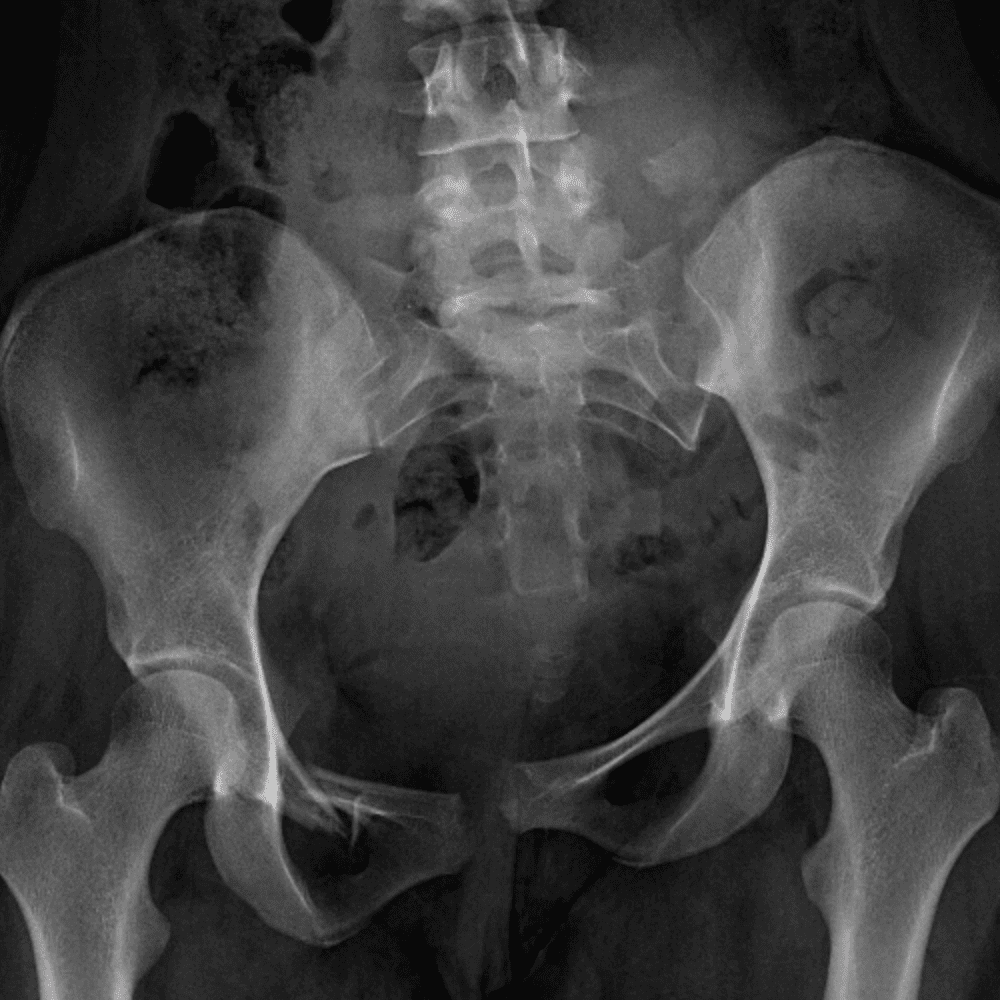

通过包含微妙或困难的病例和一些正常病例来模拟值班。